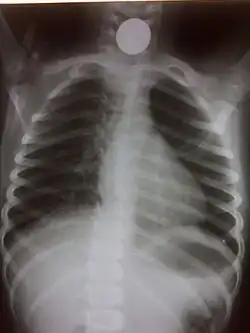

If the person who swallowed the foreign body is doing well, usually an x-ray image will be taken which will show any metal objects, and this will be repeated a few days later to confirm that the object has passed all the way through the digestive system. Also it needs to be confirmed that the object is not stuck in the airways, in the bronchial tree.